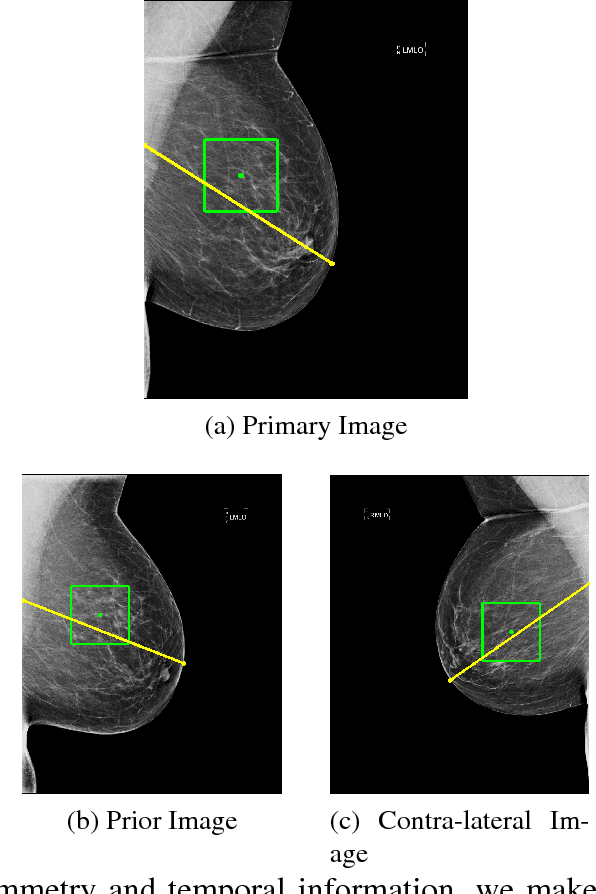

We investigate the addition of symmetry and temporal context information to a deep Convolutional Neural Network (CNN) with the purpose of detecting malignant soft tissue lesions in mammography. We employ a simple linear mapping that takes the location of a mass candidate and maps it to either the contra-lateral or prior mammogram and Regions Of Interest (ROI) are extracted around each location. We subsequently explore two different architectures (1) a fusion model employing two datastreams were both ROIs are fed to the network during training and testing and (2) a stage-wise approach where a single ROI CNN is trained on the primary image and subsequently used as feature extractor for both primary and symmetrical or prior ROIs. A 'shallow' Gradient Boosted Tree (GBT) classifier is then trained on the concatenation of these features and used to classify the joint representation. Results shown a significant increase in performance using the first architecture and symmetry information, but only marginal gains in performance using temporal data and the other setting. We feel results are promising and can greatly be improved when more temporal data becomes available.